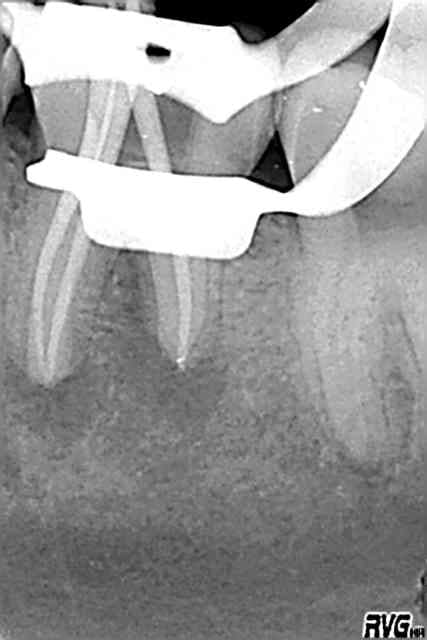

à moi, 26mm de bonheur (j'ai mis la digue mais pas de radio perop)

R2 qk1svf - Eugenol